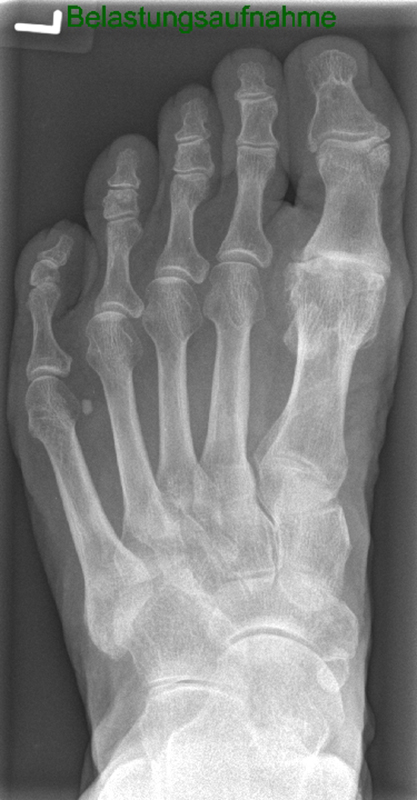

• Röntgenaufnahmen des Vorfußes (unter Belastung) im dorsoplantaren und seitlichen Strahlengang (Abb. 1a+b)

• Beurteilung des Erkankungsstadiums anhand der typischen Arthrosekriterien (Einteilung nach Regnauld). Beurteilung des Intermetatarsal-Winkels (IMA), des Hallux valgus-Winkels (HVA), da nur geringe Korrekturmöglichkeit durch die Osteotomieebene, darüber hinaus evtl. zusätzliche basisnahe MT-I-Korrektur notwendig